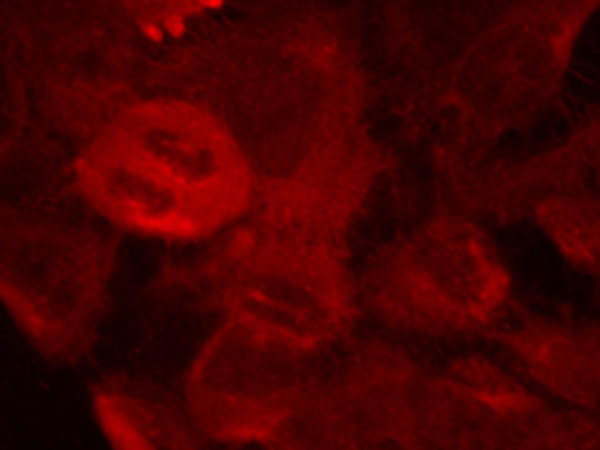

Applications:

WB, IHC, IF

Positive control:

Hela cells

Recommended dilution:

100-200